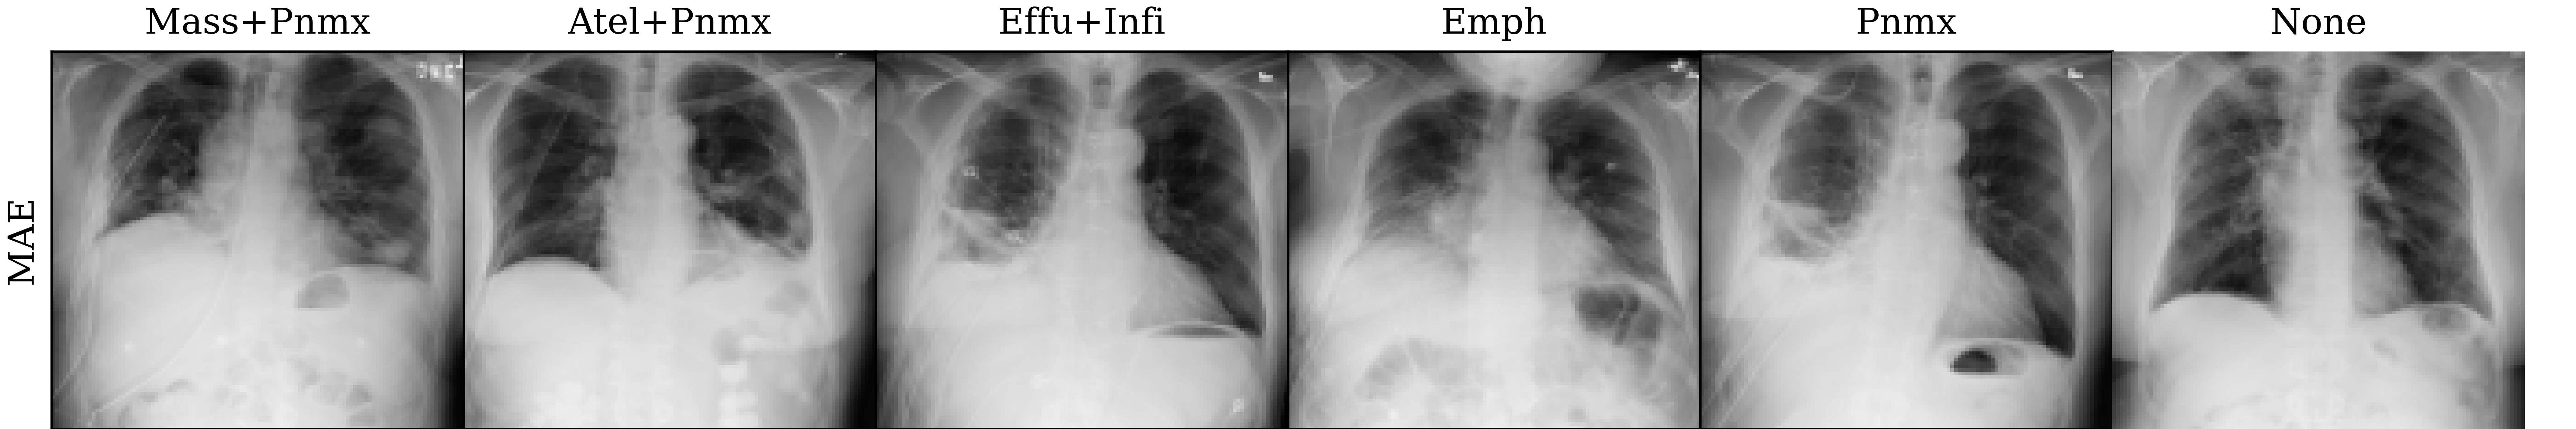

Lastly, we visualize the nearest neighbors in the embedding space of MoCo-v3 and MAE pre-trained models to yield insights into the pre-trained representations. To this end, we extract the last layer representations (after the layer norm) for both the train and test sets of ChestXray14. For each image in the test set, we compute the 5 nearest neighbors from the train set. The results are visualized in Figure 4, which reveals that the nearest neighbors of both MoCo-v3 and MAE largely preserve the overall shape of the query image. Additionally, we also perform a quantitative analysis by assigning the label of the nearest neighbor as the prediction for the query image. Under this nearest neighbor classification setting, MoCo-v3 has a slightly higher mAUC than MAE (52.7 vs 52.3), indicating that its pre-trained features are more linearly separable. This finding is in line with the observations made by He et al. (2022), who observed that the MoCo-v3 features are more linearly separable than MAE features. However, it is worth noting that despite MAE features being less linearly separable than MoCo-v3 features, the former captures more powerful non-linear features. This translates to stronger downstream models when the networks are fine-tuned instead of being used as fixed feature extractors, as evidenced by the superior fine-tuning results presented in Section 4.1.